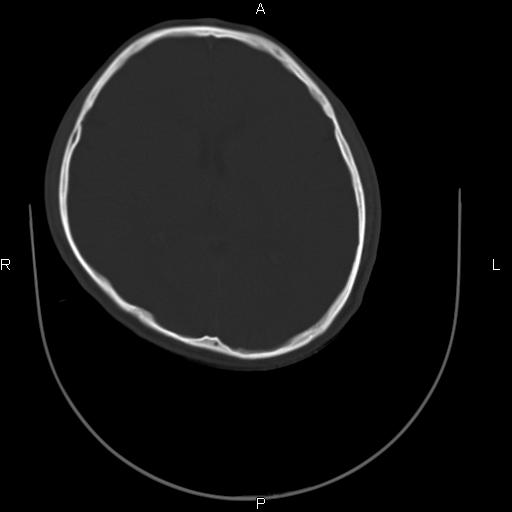

标题: CT27115:大家看一看,这孩子的颅骨表现?

两名中学生打架,脑质内未见异常,未上传。

两例——颅骨结构正常,未见明显骨折征象。

感觉第2个颅缝密度高,额顶部板障有点厚,正常变异?地中海贫血?

以下是引用37度在2010-6-15 19:31:00的发言:[br]感觉第2个颅缝密度高,额顶部板障有点厚,正常变异?地中海贫血?